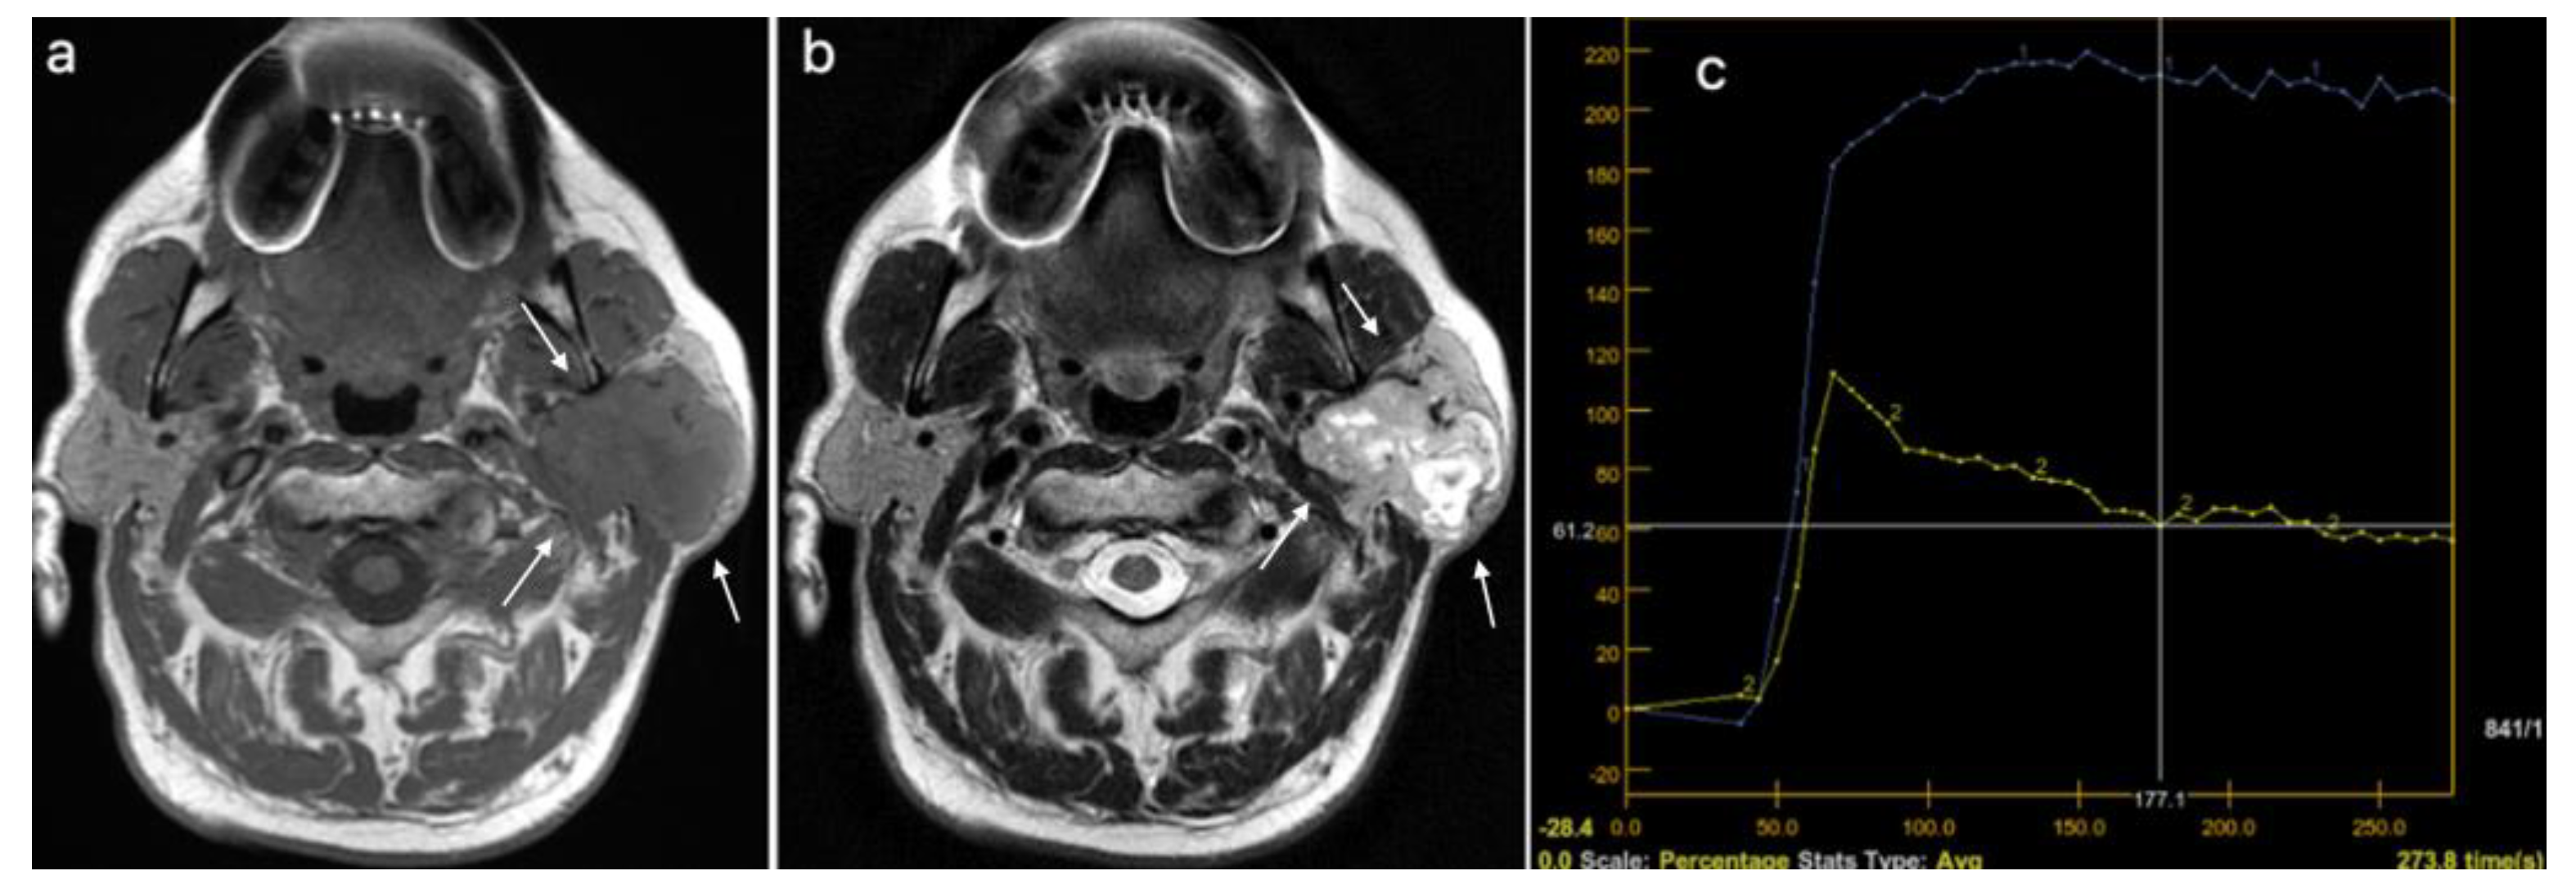

| DCE MRI*–TIC curve+, n (%) | 0.382 | ||

| Type A | 16 (29.63) | 1 (9.09) | |

| Type B | 18 (33.33) | 5 (45.45) | |

| Type C | 20 (37.04) | 5 (45.45) | |

| DCE MRI, TIC curve grouped (A, B vs. C), n (%) | 34 (62.96) | 6 (54.5S5) | 0.737 |

| DCE MRI, TIC curve, n (%) | <0.001 | ||

| Type A | 14 (73.68) | 0 (0) | |

| Type A, C | 1 (5.26) | 0 (0) | |

| Type B | 3 (15.79) | 11 (37.93) | |

| Type C | 1 (5.26) | 18 (62.07) | |

| DCE MRI, TTP (ms), median (IQR) | 210 (166.15–228.9) | 88.5 (82–101.9) | <0.001 |